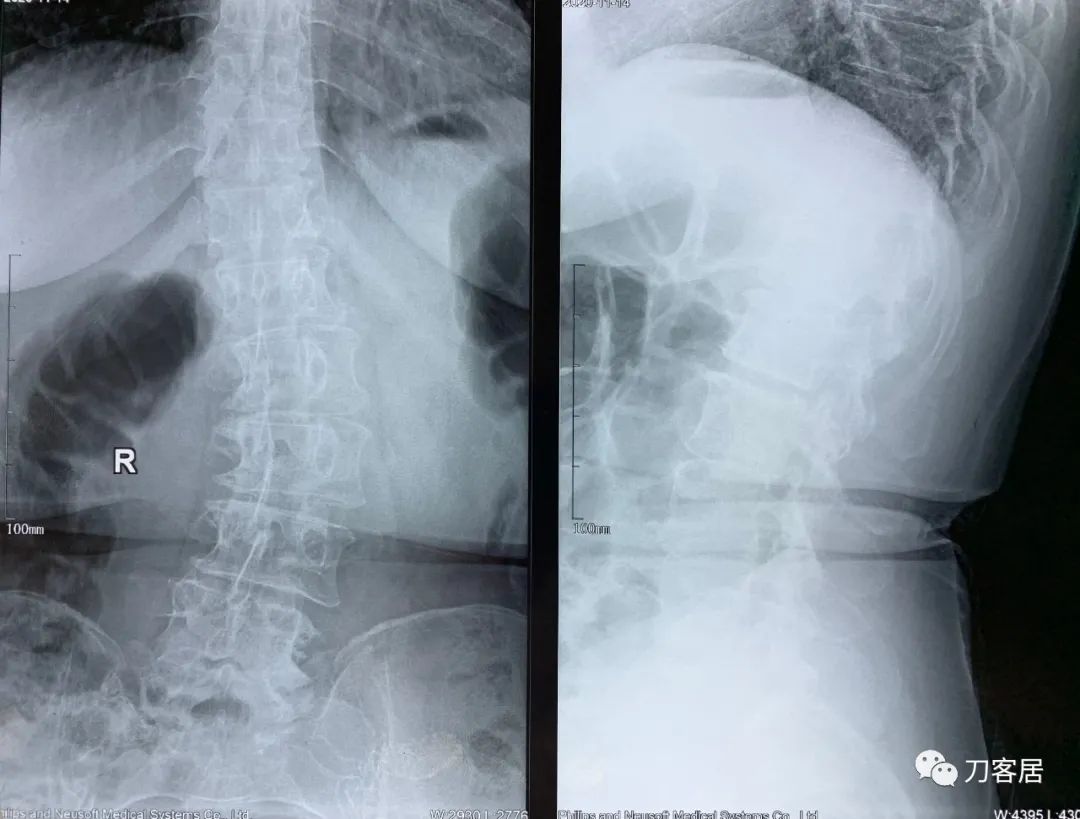

2021年5月17日,西京医院骨科门诊找我就诊,自带影像学检查资料提示腰椎侧弯,腰3-4,腰4-5椎间盘突出,黄韧带肥厚,椎管狭窄。

建议其查双光子骨密度,骨盆正位片以及腰椎间盘平扫。腰椎正侧位X线片以及动力位片,站立位脊柱全长正侧位X线片,以了解其是否有骨质疏松,并了解脊柱侧弯情况,腰椎局部X线表现情况和腰椎间盘突出和椎管狭窄情况。

从这个患者的影像资料分析,颈椎间盘突出问题不大,没有明确的上位神经元损伤表现,所以,不考虑颈椎和胸椎问题。腰椎侧弯畸形,但不严重。因为存在腰椎侧弯,使得腰椎MRI在扫描切面的时候,显示的椎间盘突出或椎管狭窄会有一定的误差,所以,又加做了经椎间盘的CT平扫,影像表现并不严重,综上,腰椎间盘突出,腰椎管狭窄,腰椎侧弯,不考虑手术治疗。同时,患者的主要痛苦是心理疾病,而不是器质性疾病,所以,以心身疾病治疗为主。虽然患者骨密度检查结果提示正常,但X线片显示骨质疏松,且其症状也与骨质疏松的症状有符合之处,比如静息痛,不能入睡,动作及姿势变换时痛加重等,所以,给予实验性抗骨质疏松治疗,以观疗效。